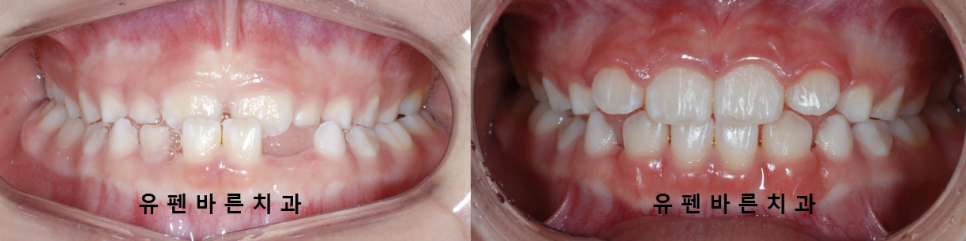

1차 교정 (소아교정)을 통해

반대교합을 해결하여

올바른 성장과 함께

안모 또한 개선된 모습을

확인 해 보실 수 있습니다 :)